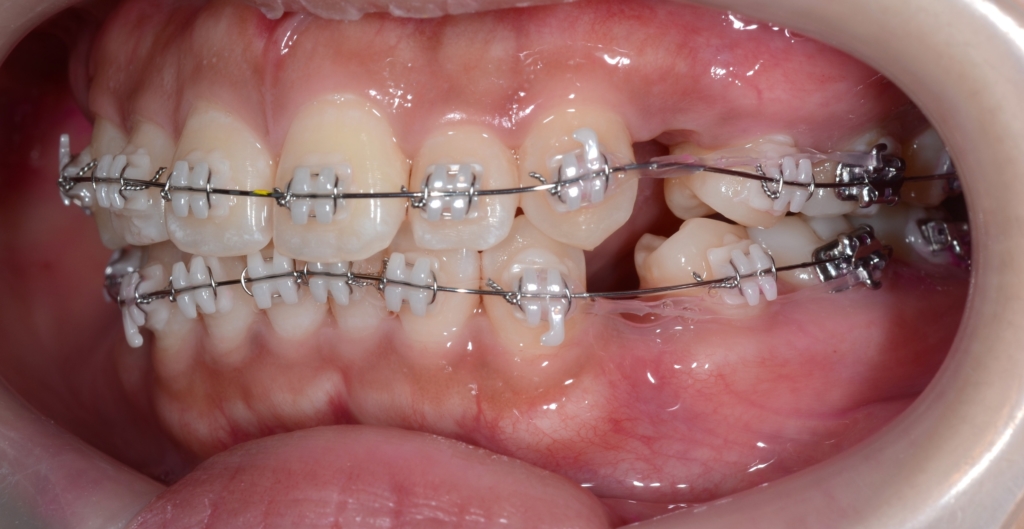

順調にステップが進み、前歯を最大限に引っ込めるステップに入りました。

【上の歯列の更なる後方への移動を図る】

隙間分はしっかり引っ込めたのですが、元の噛み合わせが上顎前突傾向でしたので、出っ歯が残ってしまいました。 そこで、より引っ込んだ下の歯列に上の歯列を引っ込めて合わせるという次のステップに進めることにしました。

あらためて、上顎にアンカースクリューを植立しました。

アンカースクリューを用いて矯正力を加えることで、上顎歯列全体を後方へ移動させて、口元の見た目の更なる改善を図ります。

同じことをしている方の写真をイメージ写真としてあげています。